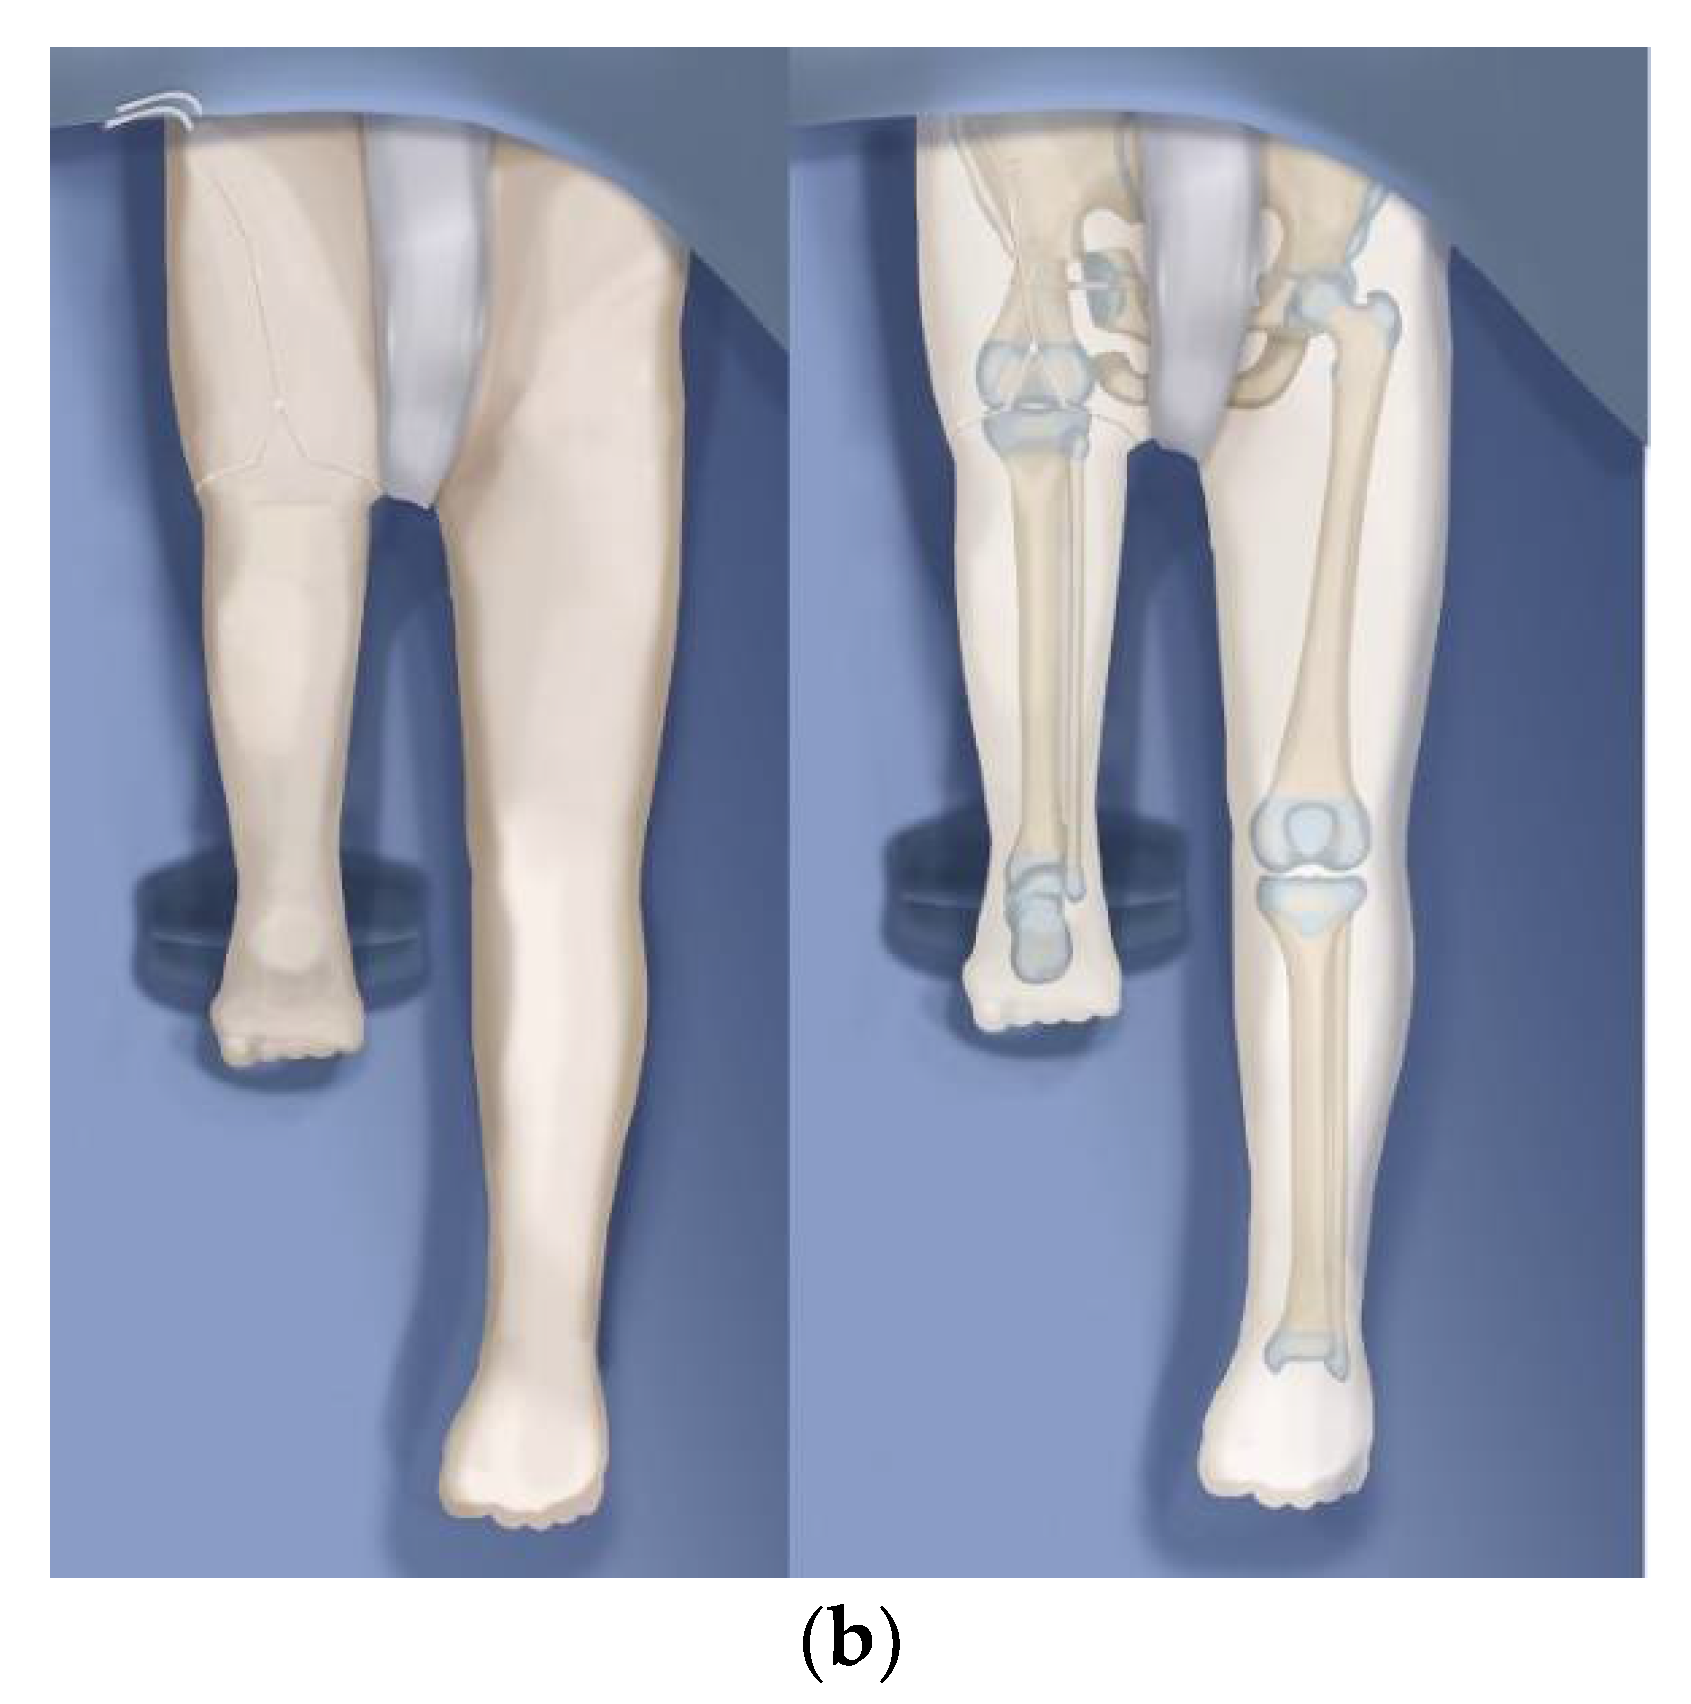

As a result of the high rate of wound complications we now use a plastic surgeon to close the incision at the end of the surgery. This has reduced our wound complication rate. Dr. Mark Pinsky the plastic surgeon we use has modified the incision as shown in Figure 8a,b. Prior to closure, he resects one cm of all the wound edges on both sides of the wound. He shortens some parts of the flaps depending on the redundancy of the skin. He also meticulously closes the basal and interposing dead space with a multilayer closure of the wound edges. Since rotationplasty is such a long surgery taking between 6–12 h of surgery prior to the closure, using a plastic surgeon removes the exhausted orthopedic surgeon who did the surgery and replaces him/her with a fresh surgeon who is an expert at soft tissue closure.

Figure 8.

(a) Illustration of the new Pinsky incision line for Brown, Paley–Brown and Paley type rotationplasties. The 3cm equilateral triangle on the posteromedial side is located at 5 o’clock for right legs and 7 o’clock for left legs. (b) After closure of the Pinsky incision with the triangle inserted anteriorly between the flaps. The wound edges except the triangle are all resected back one cm or more before closure.